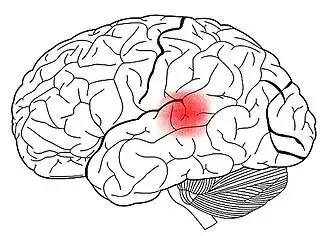

Cerebro y lenguaje

La gran mayoría de los procesos que permiten el lenguaje se llevan a cabo en diferentes áreas de asociación. Existen dos áreas bien identificadas, las cuales son consideradas vitales para la comunicación humana: el área de Wernicke y el área de Broca. Estas áreas están localizadas en el hemisferio dominante (que es el izquierdo en el 97 % de las personas) y son consideradas las más importantes en cuanto a procesamiento de lenguaje. Esta es la razón por la cual el lenguaje es considerado como una función lateralizada.[34] Sin embargo, el hemisferio no dominante también participa en el lenguaje, aunque existen cuestionamientos acerca del nivel de participación de las áreas localizadas en dicho hemisferio.[35]

El área de Wernicke, se conoce así en honor al neurólogo que la describió por primera vez. Está especialmente desarrollada en el hemisferio dominante para el lenguaje, que, generalmente suele ser el lado izquierdo. El desarrollo de esta área permite alcanzar niveles altos de comprensión y procesar la mayor parte de las funciones intelectuales del cerebro. Se encarga de la decodificación de lo oído y de la preparación de posibles respuestas. Es importante para la comprensión de palabras y en los discursos significativos.

Las diferencias funcionales entre hemisferios son mínimas y solo en algunas pocas áreas se han podido encontrar diferencias en cuanto a funcionamiento, existiendo excepciones en personas que no se observaron diferencias. Las áreas actualmente más conocidas especializadas en el lenguaje son la de Broca y la de Wernicke, aunque al hacer un proceso lingüístico es probable que todo el cerebro esté involucrado —casi indudablemente las áreas de la memoria participan en el proceso del lenguaje—. Las áreas de Broca y de Wernicke se encuentran, en la mayoría de los individuos, en el hemisferio izquierdo. Por su parte, las áreas más involucradas en la lógica y actividades intelectuales se ubican principalmente en la corteza prefrontal, teniendo quizás las áreas temporales izquierdas gran importancia para procesos de análisis y síntesis como los que permiten hacer cálculos (matemáticos); estas áreas dotan al individuo de mayor capacidad de adaptación al medio, pero con procesos de aprendizaje mucho más dilatados, y como tal más dependientes de sus progenitores durante la etapa de cría.